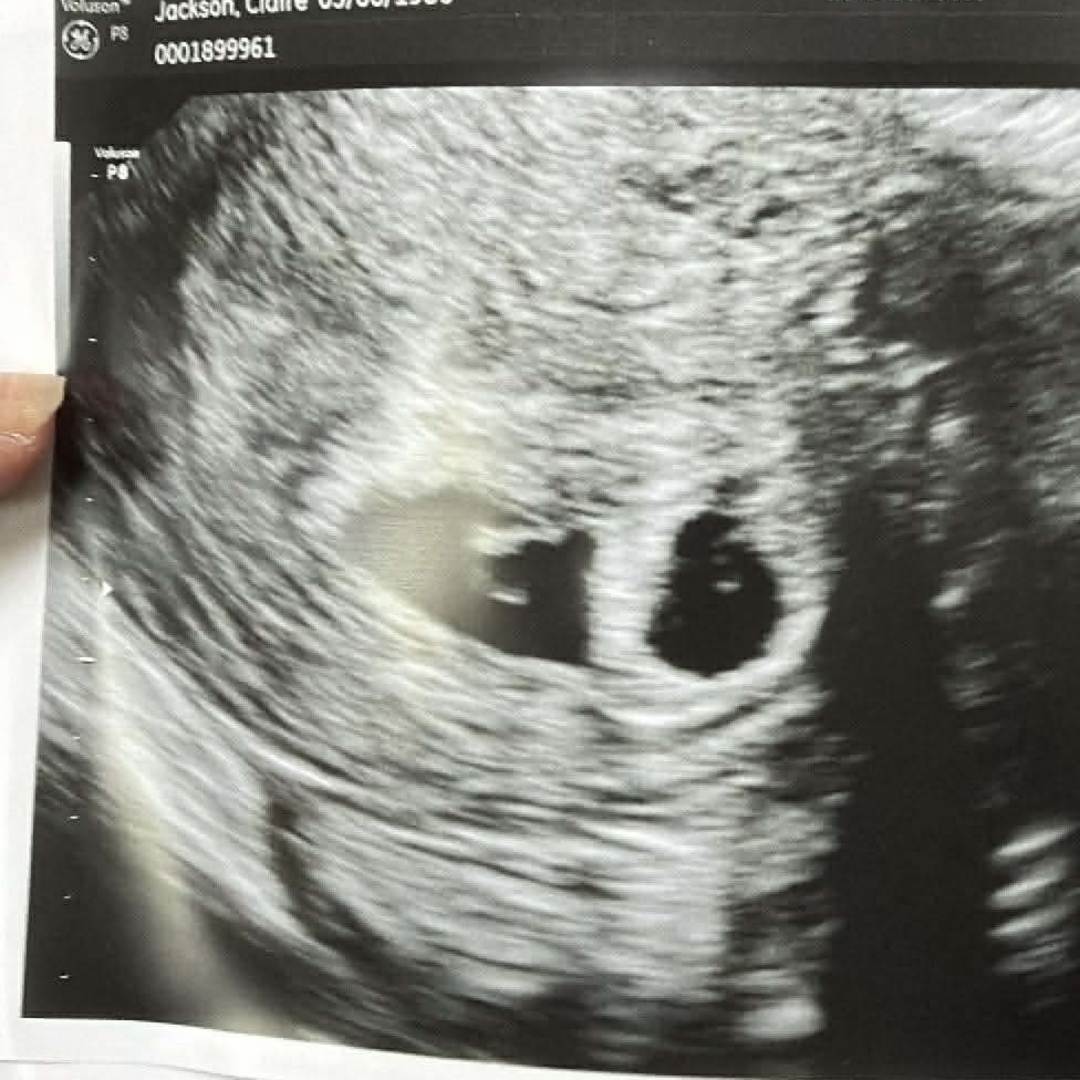

We're having twins so 2 of everything 😱